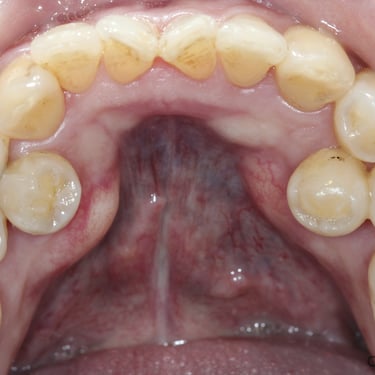

Quiste odontogénico

Un quiste odontogénico es una lesión benigna que se desarrolla en los tejidos asociados con el desarrollo dental.

Los pacientes pueden experimentar hinchazón, dolor y movilidad dental.

El tratamiento incluye la extirpación quirúrgica del quiste y la evaluación para evitar recurrencias.